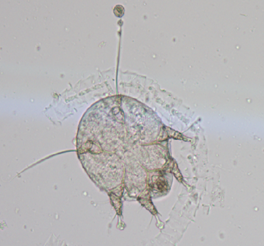

Diagnosed was made on the basis of presence of clinical signs such as, severe pruritus, crust formation, alopecia on the ears, neck, spine, tail and legs. For confirmation skin scraping was taken and processed that revealed presence of microscopic mite (Figure 4).

Figure 4 Microscopic view of Notoedric mange mite.